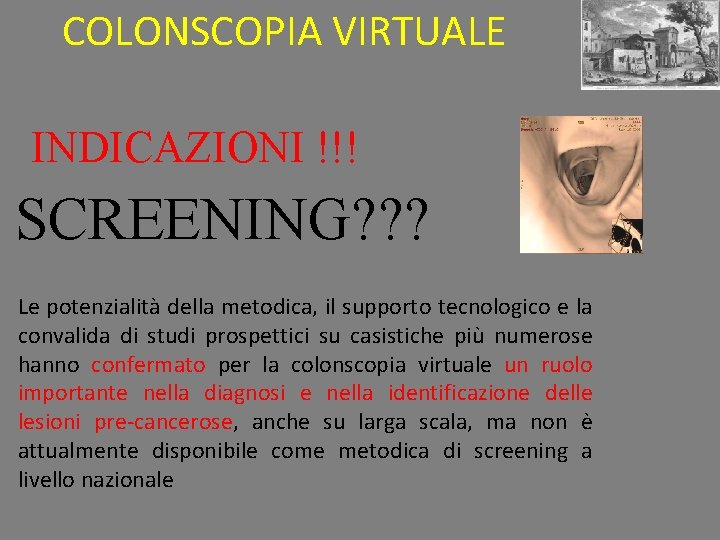

COLONSCOPIA VIRTUALE INDICAZIONI !!! SCREENING? ? ? Le potenzialità della metodica, il supporto tecnologico e la convalida di studi prospettici su casistiche più numerose hanno confermato per la colonscopia virtuale un ruolo importante nella diagnosi e nella identificazione delle lesioni pre-cancerose, anche su larga scala, ma non è attualmente disponibile come metodica di screening a livello nazionale